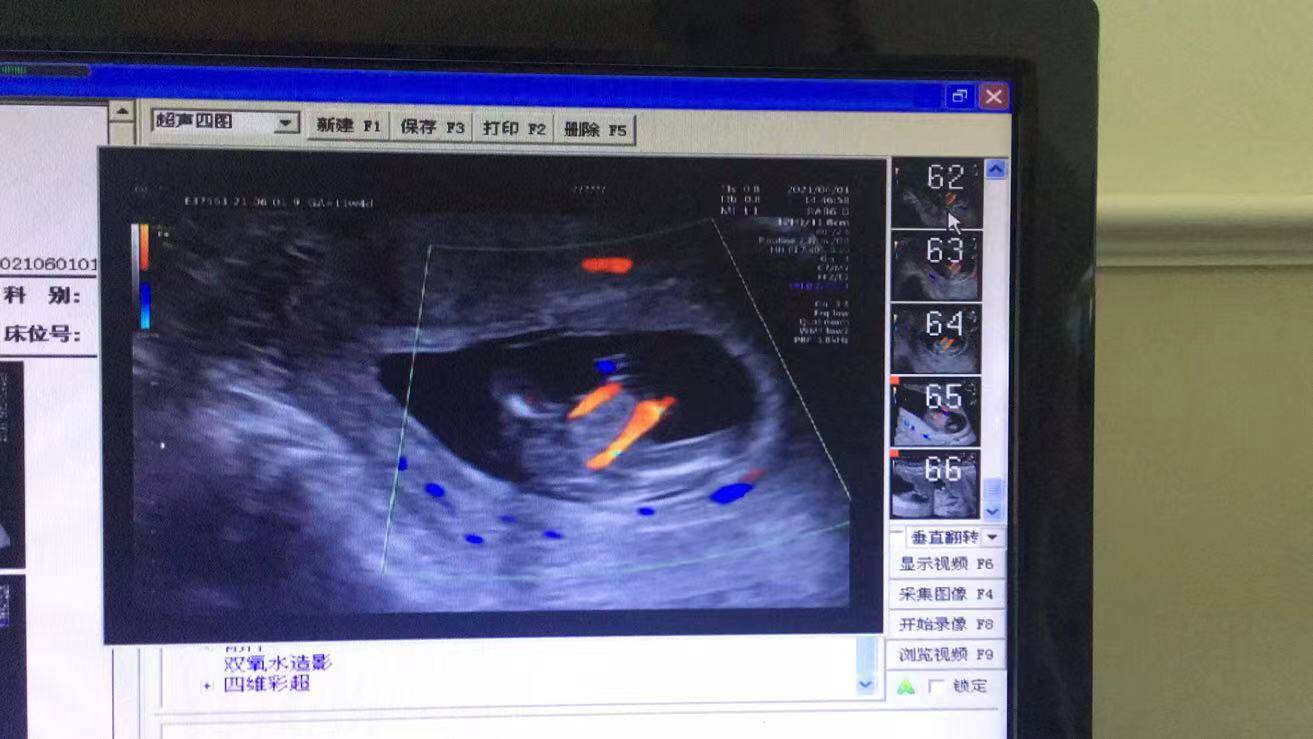

原來(lái),前幾天,懷孕11周的她來(lái)到武漢仁愛(ài)醫(yī)院超聲科做了NT(頸項(xiàng)透明層)檢查,發(fā)現(xiàn)腹中胎兒有些異樣,寶寶的右腳缺失,脊柱部也有異常,超聲科醫(yī)生立刻叫來(lái)了超聲科王娟主任進(jìn)行再次檢查,經(jīng)過(guò)30分鐘的仔細(xì)探查后,王主任終于看清楚了胎兒的情況,并最終確診:“腹中胎兒右小腿長(zhǎng)骨發(fā)育不良,右腳缺失,脊柱腰骶段排列異常,會(huì)陰部包塊,考慮泄殖腔外翻可能。”王娟介紹。

(王女士NT檢查結(jié)果)